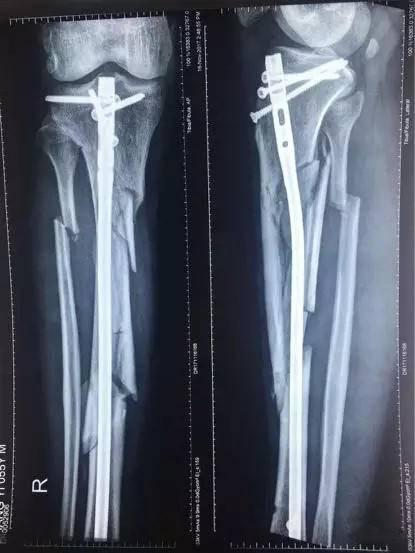

(张毅被打断的腿X光照片)